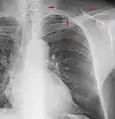

The margins of the supraclavicular fossa are often visible on chest X-ray